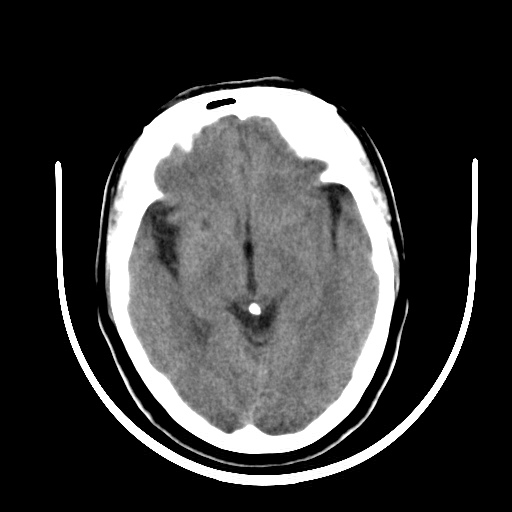

标题: CT16579:女 65岁间断性抽搐. [打印本页]

标题: CT16579:女 65岁间断性抽搐.

考虑右侧颞叶脑软化灶并脑穿通畸形;建议必要时行进一步检查。

右侧蛛网膜囊肿

右颞叶脑软化灶。余未见明显异常。

考虑右颞叶脑软化灶

右颞叶软化灶,右基底节区腔隙性脑梗塞;